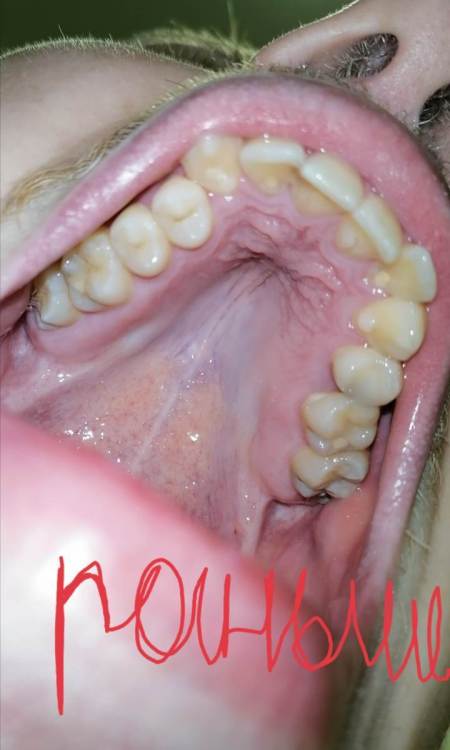

Фотографий много, но приложу три главных: 1) РАНЬШЕ до появления налёта 2) ДО всех процедур очистки 3) ПОСЛЕ всех процедур очистки

Screenshot_20230129_234741.jpg